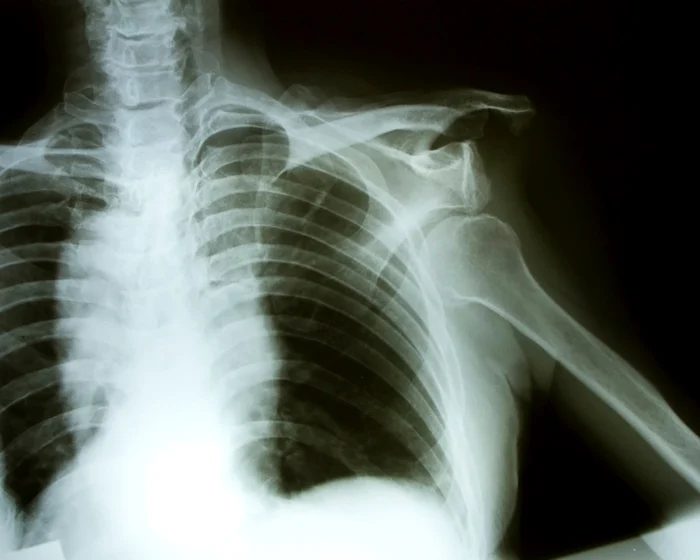

Tusea, strănutul şi chiar cea mai mică smucitură, cum ar fi simpla trecere peste obstacolele pentru reducerea vitezei, înseamnă un coşmar pentru o britanică în vârstă de 20 de ani. Lauren Harry spune că un efort atât de banal duce la dislocarea umărului său chiar şi de zece ori pe zi.

Medicii cred că suferă de sindromul Ehlers-Danlos (SED), o afecţiune genetică ce se manifestă prin modificări ale colagenului, materialul care asigură structura şi rezistenţa tegumentului şi a ţesutului osos. Colagenul ei este atât de slab, încât nu-i poate susţine membrele.

Lauren acuză dureri de picioare de când avea 11 ani, dar i s-a spus că sunt durerile fireşti ale creşterii. La 15 ani a căzut cu cârjele în timp ce participa la un festival, rănindu-şi umărul. De atunci, umerii şi încheieturile, inclusiv genunchii şi degetele, i se dislocă frecvent, potrivit „Daily Mail“.

Ea a fost supusă la cinci intervenţii medicale pentru stabilizarea umerilor, dar problema nu a putut fi rezolvată. „Am suferit câteva intervenţii care mi-au fixat oasele pentru o perioadă, dar nu a durat mai mult de nouă luni până la o nouă dislocare. Umerii mei se dislocă de 10 ori pe zi, fie că strănut, tuşesc sau trec peste un obstacol cu limitare de viteză“, a declarat Lauren.